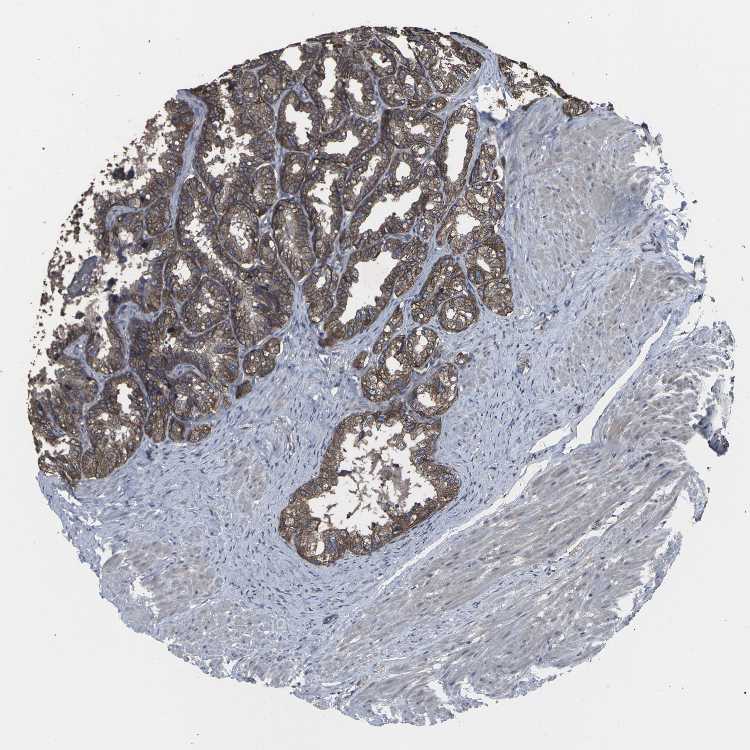

TISSUE PRIMARY DATA SEMINAL VESICLE Show tissue menu

SEMINAL VESICLE - Antibody stainingi

Antibody staining in the annotated cell types in the current human tissue is reported as not detected, low, medium, or high, based on conventional immunohistochemistry profiling in selected tissues. This score is based on the combination of the staining intensity and fraction of stained cells.

Each image is clickable and will lead to virtual microscopy that enables deeper exploration of all samples and also displays staining intensity scores, fraction scores and subcellular localization as well as patient and tissue information for each sample.

Antibody HPA063708Antibody HPA064435Antibody CAB010297

Glandular cells HighMediumHigh